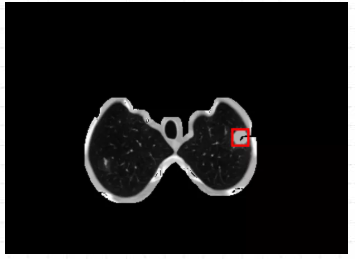

箭头指的地方可看见检测结果,可以说利用ModelArts平台训练出来的肺结节检测模型检测效果是很棒的。(直接看太小的话,可以点开图片放大看)

从最后实验的结果对比图来看,可以说利用ModelArts平台训练出来的肺结节检测模型检测效果是很棒的,虽然存在一定的肺结节病灶假阳性标记,但是这在小样本数据集的人工智能医疗检测中是会出现的情况。毕竟对于人工智能医疗检测模型来说,只用了300张标注图片就能达到这样的效果,真的让人感到惊喜。